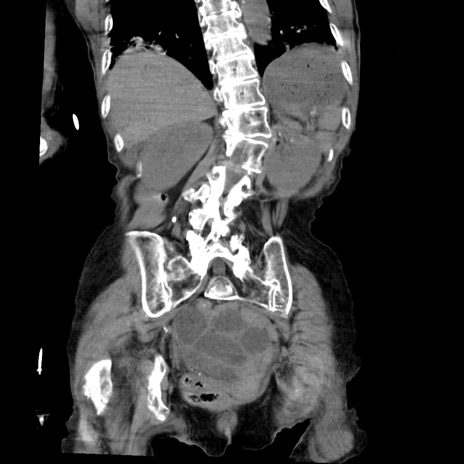

症例27(冠状断像)

【症例】80歳代女性

【主訴】嘔吐、腹痛

【現病歴】数時間前より嘔吐あり。心窩部痛出現し、徐々に右下腹痛あり。その後も数回嘔吐あり救急搬送となる。

【既往歴】左大腿骨頚部骨折手術

【身体所見】腹部は膨隆しているが軟らかく圧痛なし。腸雑音はやや亢進。

【データ】WBC 12000、CRP 19.05